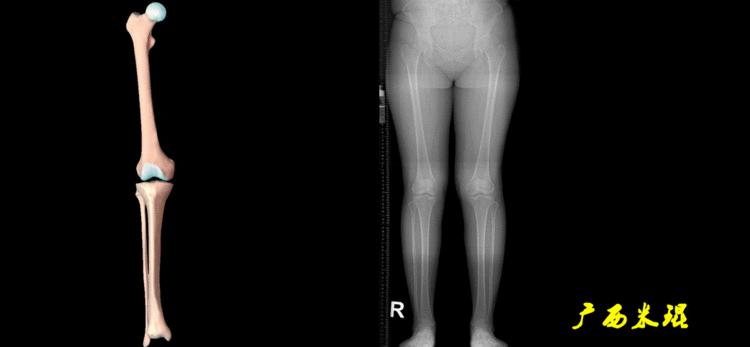

机械轴要分前后位及侧位,站立前后位(也就是冠状面)股骨头中心与踝关节中心的连线通过膝关节中心,这是下肢的机械轴线,也就是下肢力线,常说Mikulicz线。冠状面的力线评估在临床工作中最常用、最基础、最重要。

也就是下肢的负重轴,它是身体的纵轴线,与地面垂直,由于双髋比双踝的距离宽,所以垂直轴与下肢力线(机械轴)存在3°的外翻。

最常见的下肢畸形发生于冠状面,即膝内外翻畸形,冠状面的对线异常通过应用“对线异常检验”进行分析,机械轴的偏移(MAD)表现为对线异常。

膝内翻是指下肢力线通过膝关节中心点内侧,距中点2mm以上,偏内超过15mm为显著膝内翻。膝外翻是指下肢力线通过膝关节中心点外侧,距中点2mm以上,偏外超过10mm为显著膝外翻。